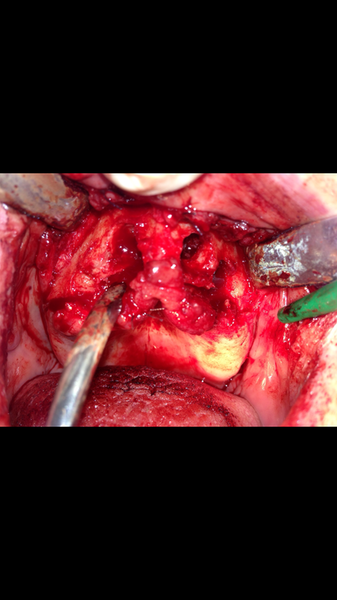

Implantologia avanzata con contestuale rimozione impianti e cisti

Estrazione di un canino incluso e contestuale inserimenti di impianto e innesto osso eterologo